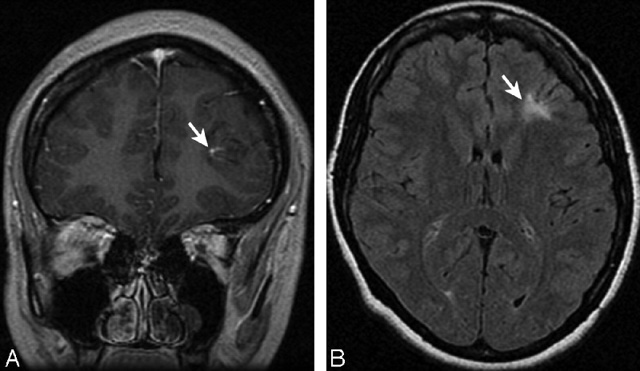

На представленных фото чётко видны сосудистые аномалии головы, для лечения которых нужно обратиться в неврологию.

- дуплексное сканирование сосудов шеи и головы, позволяющее оценить состояние артерий, вен и скорость тока крови;

- магнитно-резонансную томографию с контрастом, при помощи которой легко увидеть аневризму, гематому, деформацию и сужение диаметра стенок;

- компьютерную томографию с использованием контрастного вещества. Трёхмерное изображение позволяет изучить коронарные сосуды и обнаружить мельчайшие аномалии;